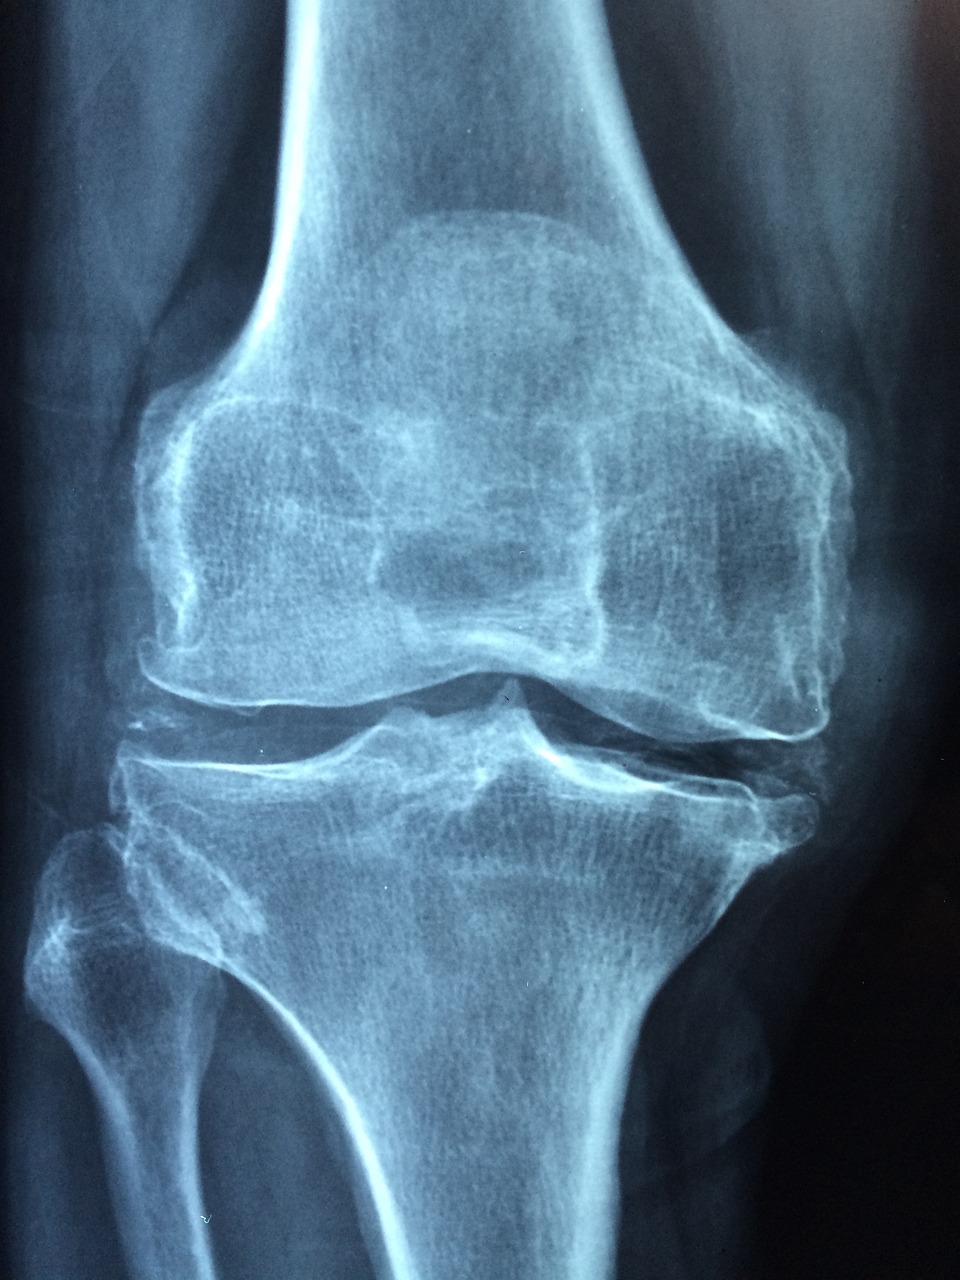

3.골절 발생 증가: 골다공증은 뼈의 약화로 인해 일상적인 활동 중에도 비교적 경도의 외부 충격에도 골절이 발생할 수 있는 위험성을 증가시킵니다. 특히, 골다공증으로 인한 골절은 골밀도 감소로 인해 이례적으로 발생할 수 있습니다.

4.퇴행성 포함체영양증 증상: 골다공증은 일반적으로 나이가 들면서 발생하는 기타 뼈 질환(예: 관절염)과 관련된 증상도 유발할 수 있습니다.